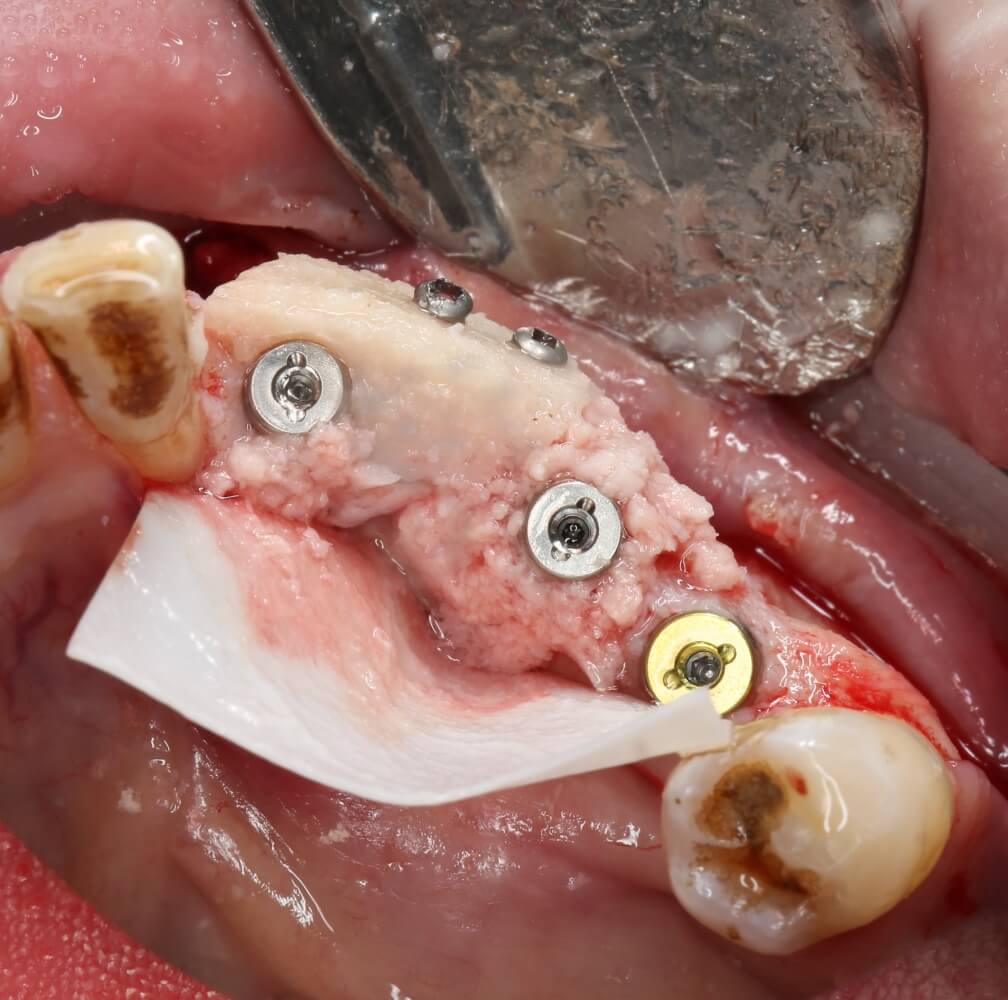

Рекомендации по установке имплантов. Для всех. Часть V.